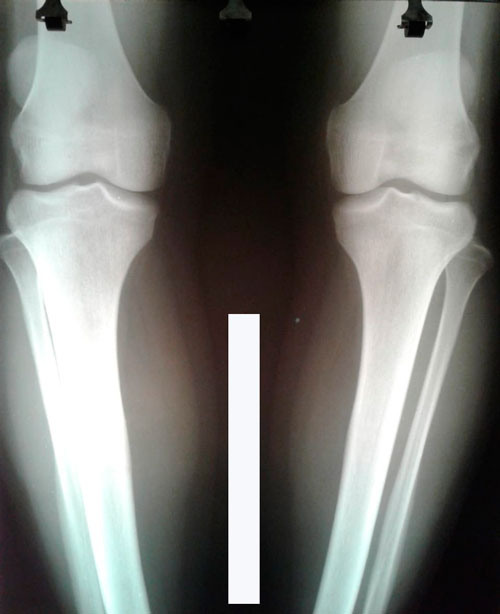

Исходник - 25 лет.

Дата операции 06.08.2018г.